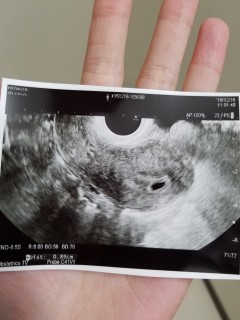

3日前には確認できなかった胎嚢が、無事に5w0dで確認できました!大きさは不明ですが、外枠のメモリから判断して、4-5㎜かと思われます。次の診察は9日後です。無事に胎芽・心拍を確認できますように…!

最終月経開始日1/18。3/6に陽性。3/7胎嚢見えず。3/15に胎嚢確認、7ミリ。次は2週間後に診察!心拍確認できますように!